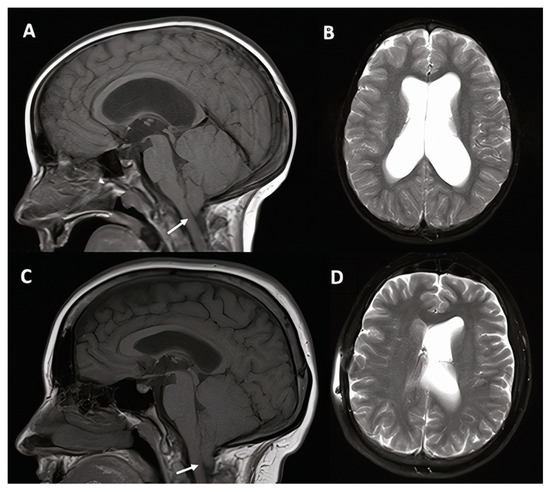

3.1.1. Case #1. Hydrocephalus with Chiari I Malformation

| 1 | 6 y, F |

|